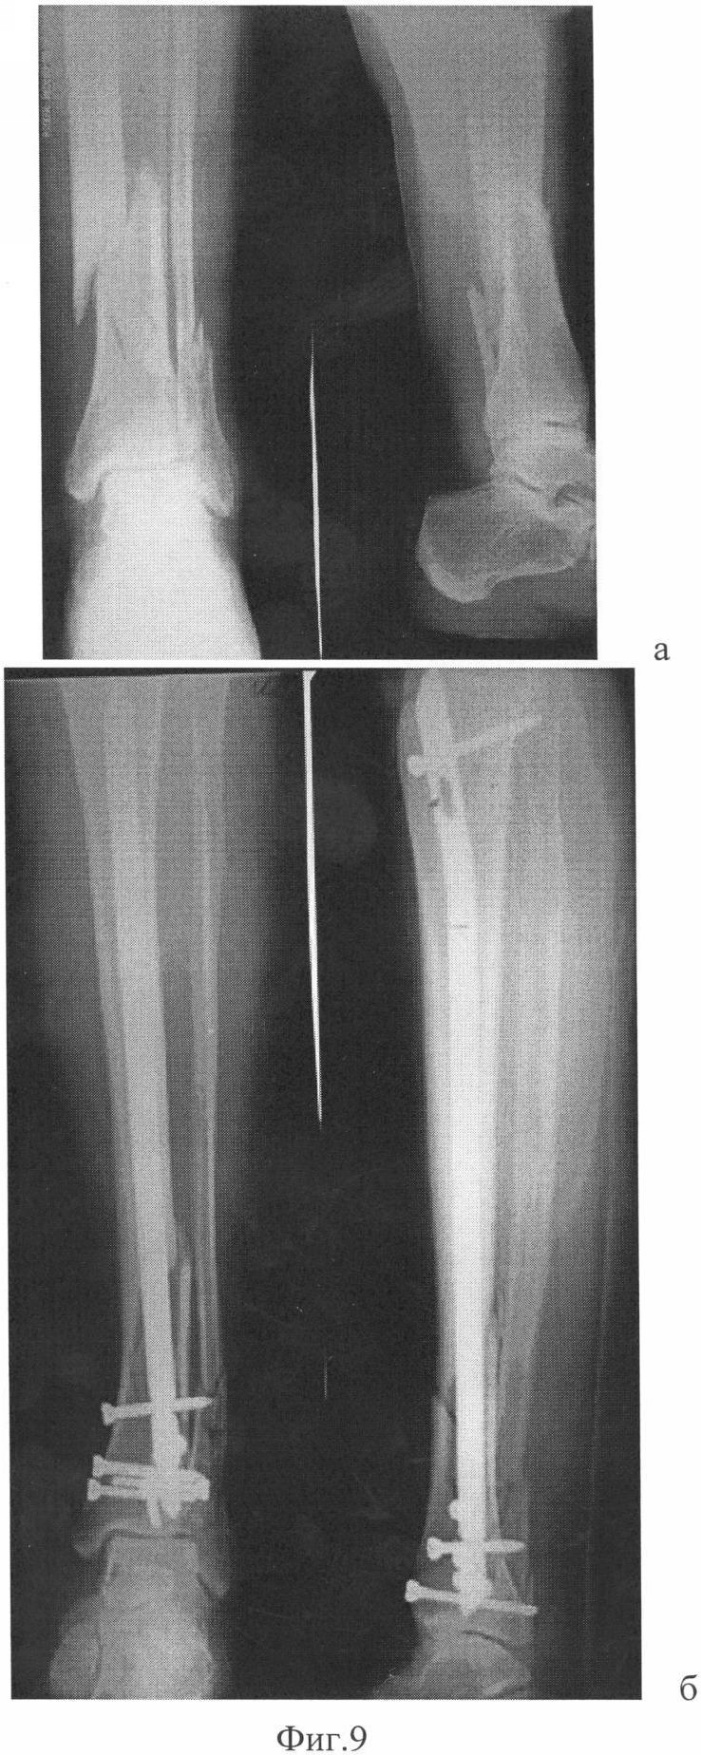

2. Высокий проксимальный перелом большеберцовой кости.

На Фиг.8 – рентгенологическая картина с введенными отклоняющими спицами: а – вид спереди; б – вид сбоку.

3. Дистальный перелом большеберцовой кости.

На Фиг.9 представлены рентгенограммы: а – до лечения; б – итог операции.